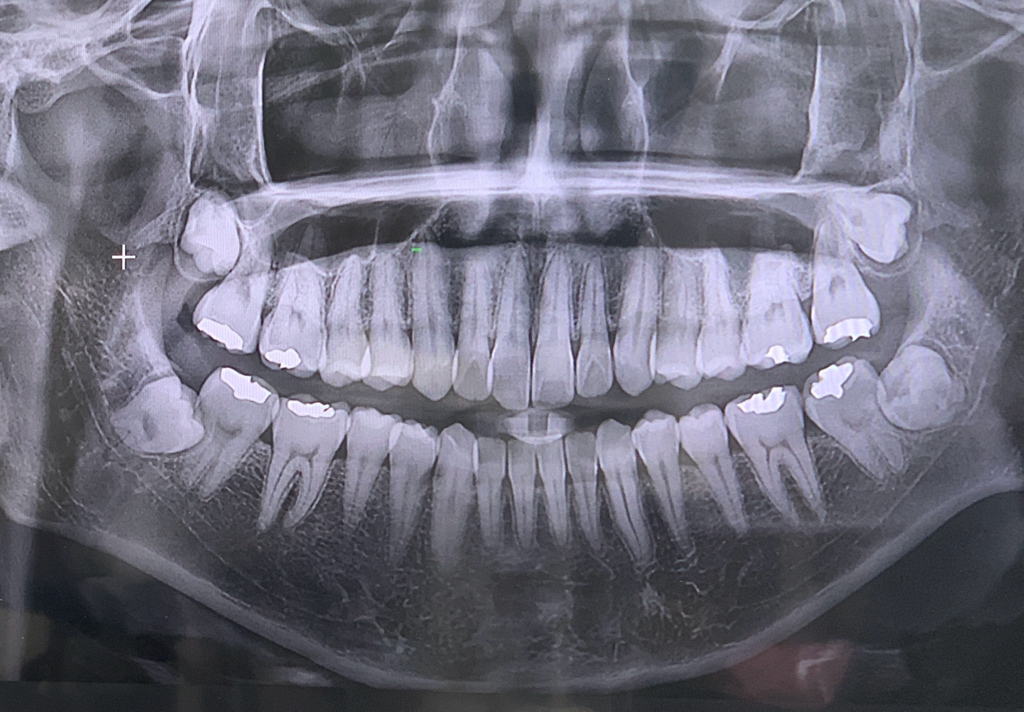

1. 첫번째가 2년전 두번째 사진이 올해찍은 엑스레이인데요 현재 나이가 27살인데 심미목적으로 치아교정을 진행중입니다.

• 2번 째 사진

아래쪽 엑스레이는 약간 잘못나온것처럼 보입니다. 그걸 감안해서보더라도 치근흡수가 많이 일어 난거 같지는 않습니다.

4. 파노라마 사진은 왜곡도 많이 되어 있고 아래 앞니가 앞으로 기울어져 있을 경우(flaring) 아주 짧게 보이는 경우도 있습니다. 따라서 아래 앞니의 각도가 어떤지 실제 모습을 봐야 정확히 알 수 있습니다. 아래 앞니 각도가 정상이라는 전제하에 치근은 평균보다 다소 짧아 보입니다.